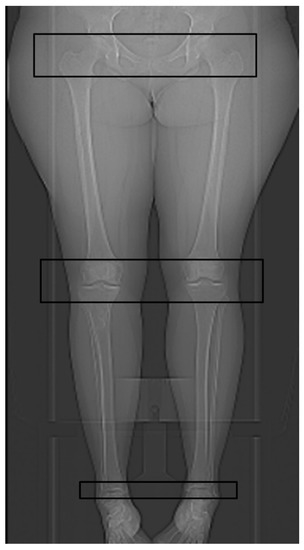

2.3. Technical Parameters of the HQ Protocol for CT Torsion Measurement of the Lower Limb

2.4. Technical Parameters of the New ULD Protocol for CT Torsion Measurement of the Lower Limb